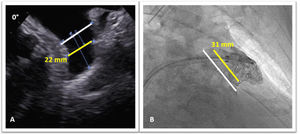

A 68-year old hypertensive man with diabetes and a history of persistent atrial fibrillation and an ischemic cerebral event, was referred for percutaneous left atrial appendage (LAA) closure. He was at high thromboembolic risk based on a CHA2DS2-VASc score of five and oral anticoagulants were contraindicated due to a firearm-related brain injury. A pre-procedure transesophageal echocardiogram (TOE) showed a LAA compatible with percutaneous closure (Figure 1A). It was performed under general anesthesia and with TOE guidance. After transseptal puncture, a windsock-shaped LAA with a landing zone of 31 mm was observed on fluoroscopy (Figure 1B). Based on TOE and fluoroscopy measurements, a 34-mm Amplatzer Amulet device was chosen and deployed in the LAA with a residual leak of 3 mm. Once in place, device stability was confirmed: tire shape of the lobe, concavity of the disk and good separation of the lobe from the disk (Figure 2-A); device lobe was aligned with appendage neck and more than two thirds of the device lobe was located distal to the circumflex artery (Figure 2B and C). The next day, he was asymptomatic and hemodynamically stable, however, a routine chest X-ray (Figure 3A) and transthoracic echocardiogram (Figure 3B and C) showed embolization of the LAA device into the left ventricular outflow tract, without impairment of mitral valve function. Because of the risk of damage to the aortic and mitral valves by the device unfolded anchoring barbs, urgent surgical device removal (Figure 4) and appendage amputation was the first line strategy and the procedure was uneventful.